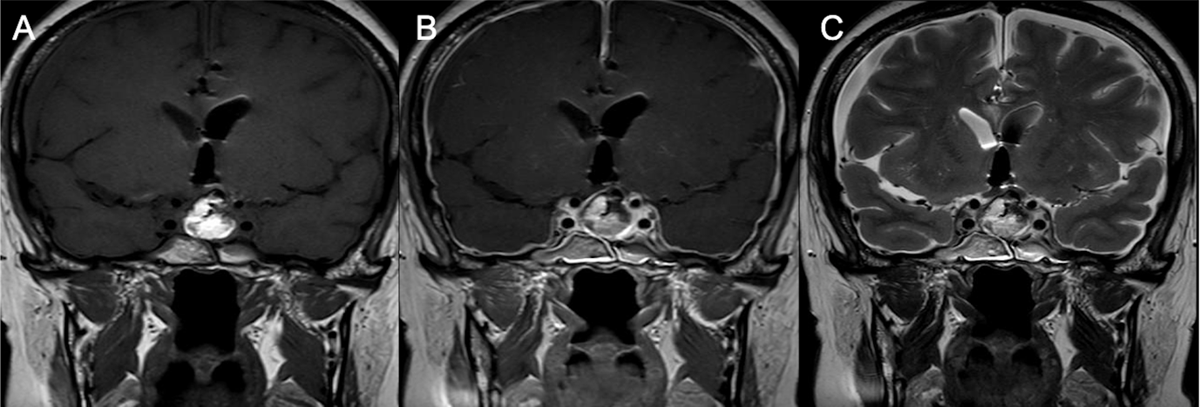

Figure 1

Intrasellar and suprasellar lesion in a 67-year-old female patient, which is hyperintense in on coronal T2WI (A), hypointense on coronal T1WI (B), and no enhancement is observed on contrast-enhanced T1WI (C) diagnosed as Rathke’s cleft cyst pathologically.